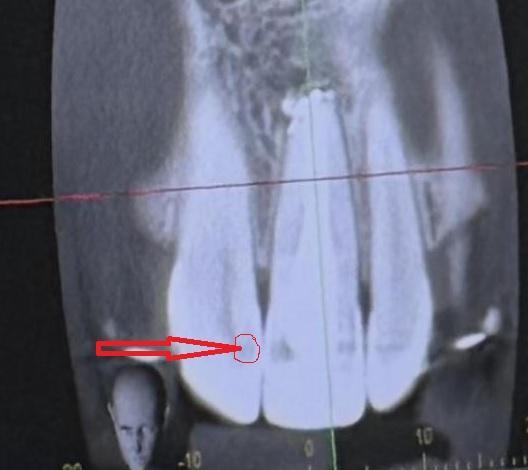

Такой вопрос. Почему может болеть зуб? Каналы пролечены. Лечили повторно 1 год назад. Сейчас начал болеть зуб. Зуб после травмы. Боль ноющая, при постукивание и нажатие не болит. Снимок 1 после пол года лечения, 2 после года лечения. После последнего снимка прошел месяц и зуб начал болеть.

Mila345, предполагаю в соседнем кариозный процесс!? Надо исключить источник боли в нём!

А уже после этого предполагать, что-то другое!

Вот полный снимок. Может смотрится что на том зубе кариес потому что дуга от брекетов засвечивает.

Mila345, может и засвечивает... Если нет других источников боли, то, скорее всего, придётся смириться с этим состоянием и ноющая боль будет периодически возникать, особенно после переохлаждения. Да, кстати: на мой взгляд "засветка" должна дать обратную картину, т.е. - белое пятно, а не тёмное! Но, каждый смотрящий на картину, видит то, что хочет видеть...